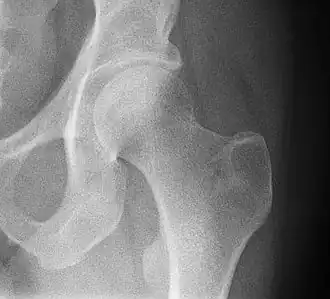

4) Данные рентгенологического обследования — выполняется рентгенография тазобедренного сустава в прямой проекции. Наличие линии перелома на рентгенограмме служит окончательным, объективным подтверждением предварительно выставленного диагноза. Иногда для постановки диагноза может потребоваться магнитно-резонансная томография или компьютерная томография.

В большинстве случаев достаточно выполнения рентгенограммы в прямой проекции. В ситуациях, когда есть подозрение на перелом шейки бедра, но оно не выявлено на рентгеновском снимке, следующим методом исследования является КТ. В редких случаях для подтверждения диагноза используется МРТ - диагностика.

Случай, демонстрирующий возможный порядок исследования изначально незаметных проявлений: